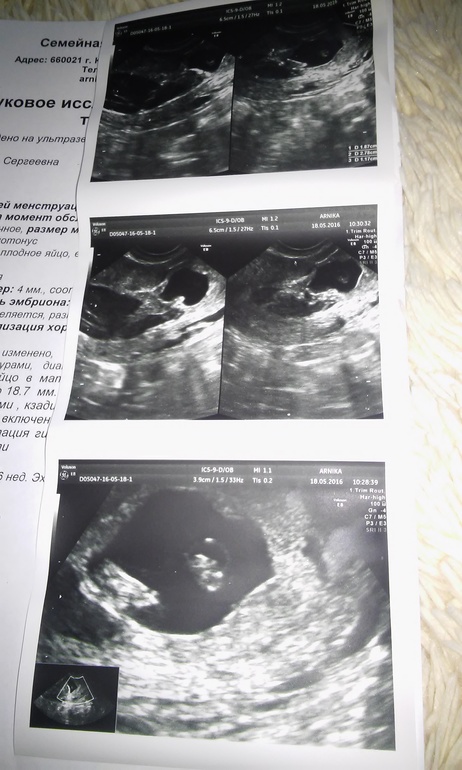

Сегодня писала о зб. Забрала УЗИ!

Беременность- 1 триместр ( только до 10 недель)Девочки забрала узи посмотрите может кто что скажет. Надежды мало но все же!

Была сегодня на узи сердцебиения нет. Кровотока тоже. Зато появилось еще одно плодное яйцо. И эмбриончик стал 5 мм.